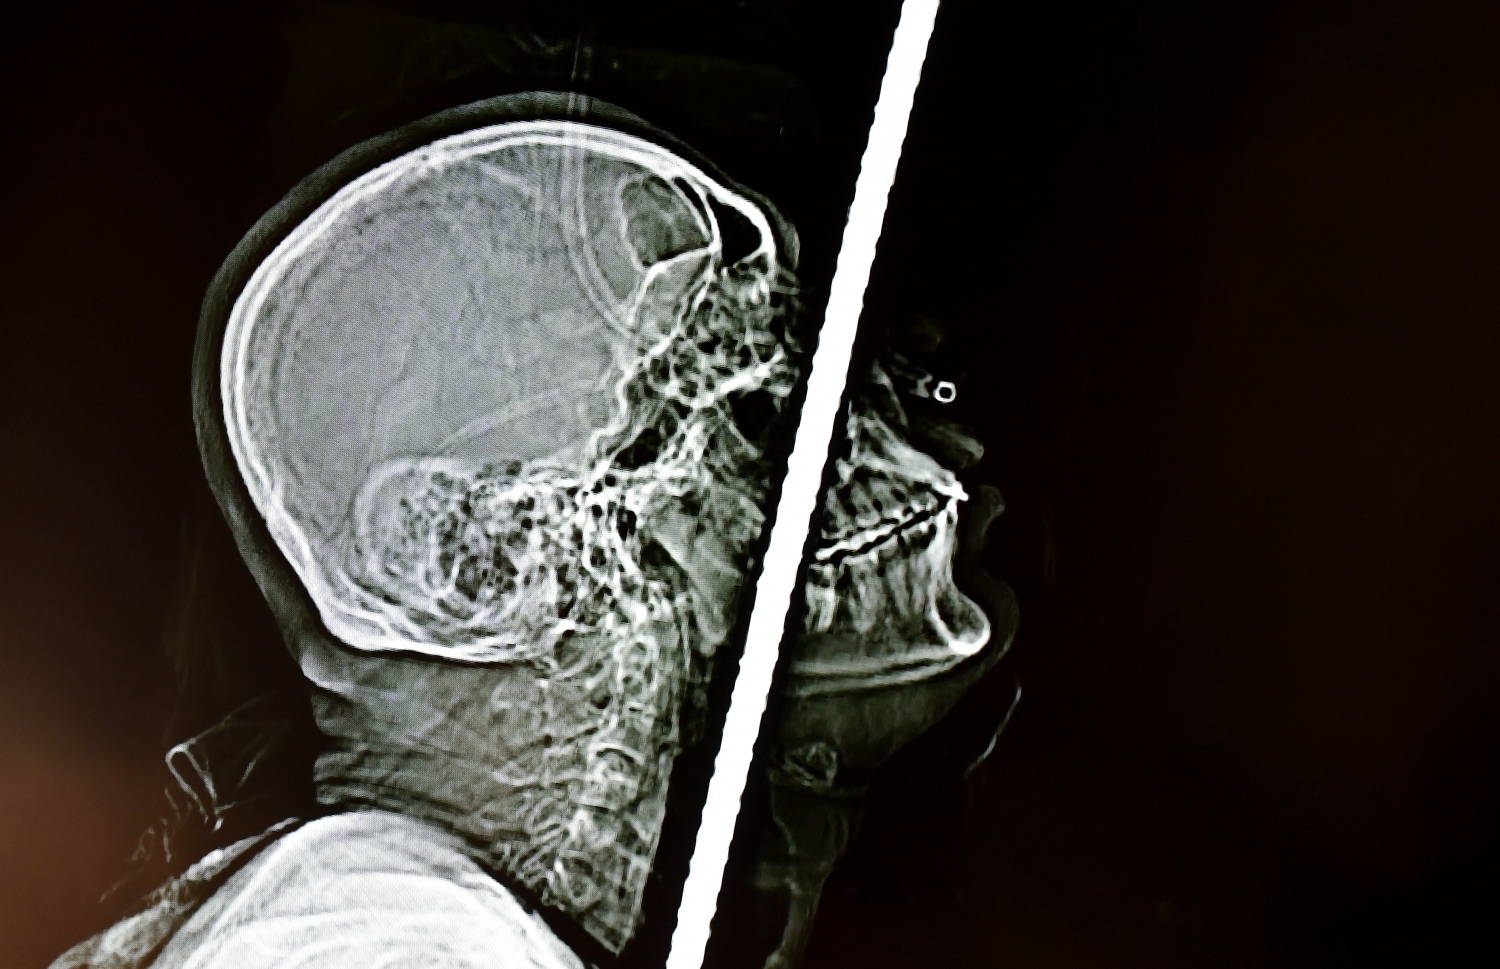

ފޮޓޯތަކުން ފެންނަ ގޮތުގައި، ނޭފަތުގެ މަތިން ހަށިގަނޑަށް ވަތް އެ ދަގަނޑު، މަތީތަލަ ފޫއަޅުވާލާފައި ކަރަށް ވަދެ، ފުރަތަމަ ގޮސް ޖެހެނީ މައިބަދައިގައި. މައިބަދައިގައި ޖެހިފައި، ތިން ބަދަ ފުނޑުވި. އޭގެ ފަހުން ފުޕާމެ އަށް ވަދެ، ފުއްޕާމެ އާއި ބަނޑާ ދެމެދުގައި އޮންނަ މަސްގަނޑު ފޫއަޅުވާލައި ބަނޑުގެ އެތެރެއަށް ވަދެ، ފުރަމޭ އަށް ވެސް ގެއްލުންވި.

ޕޭޝަންޓުގެ ގަޔަށް އެ ދަނޑު ވަދެފައި އޮތް ގޮތުގެ ސްކޭން އަދި ތްރީޑީ ފޮޓޯތަކެއް ވެސް މިއަދު ދެއްކި އެވެ. އެ ފޮޓޯތަކުން ފެންނަ ގޮތުގައި، ނޭފަތުގެ މަތިން ހަށިގަނޑަށް ވަތް އެ ދަގަނޑު، މަތީތަލަ ފޫއަޅުވާލާފައި ކަރަށް ވަދެ، ފުރަތަމަ ގޮސް ޖެހެނީ މައިބަދައިގަ އެވެ. މައިބަދައިގައި ޖެހިފައި، ތިން ބަދަ ފުނޑުވެ އެވެ. އޭގެ ފަހުން ފުއްޕާމެ އަށް ވަދެ، ފުއްޕާމެ އާއި ބަނޑާ ދެމެދުގައި އޮންނަ މަސްގަނޑު ފޫއަޅުވާލައި ބަނޑުގެ އެތެރެއަށް ވަދެ، ފުރަމޭ އަށް ވެސް ގެއްލުންވެ އެވެ. އަދި ބަނޑުގެ މަސްގަނޑު ތެރެއަށް ވަދެގެން ގޮސް، އެ ދަނގަޑު ބުރި ހުއްޓެނީ އުކުޅުވަޅުގެ ކަށިގަނޑުގައި ޖެހިފަ އެވެ.

ހަށިގަނޑު ފޫއަޅުވާލައި، ދަގަނޑެއް ވަތް ބިދޭސީ މަސައްކަތު މީހާއާ ގުޅޭ މައުލޫމާތު ދިނުމަށް އޭޑީކޭ ހޮސްޕިޓަލުން ބޭއްވި ނިއުސް ކޮންފަރެންސްގައި ދެއްކި، އެ މީހާގެ ހަށިގަނޑަށް ދަގަނޑު ވަދެފައި އޮތްގޮތް ފެންނަ ގޮތުގެ ސްކޭނަކާއި ތުރީޑީ ފޮޓޯއެއް -- ފޮޓޯ: ފަޔާޒް މޫސާ | މިހާރު